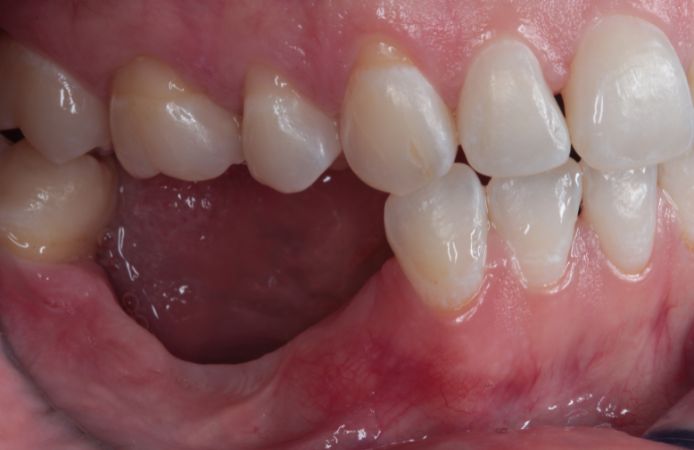

Figure 1.

Initial clinical situation. Severely resorbed posterior mandible following a previous failed attempt to insert dental implants with a split-crest technique.